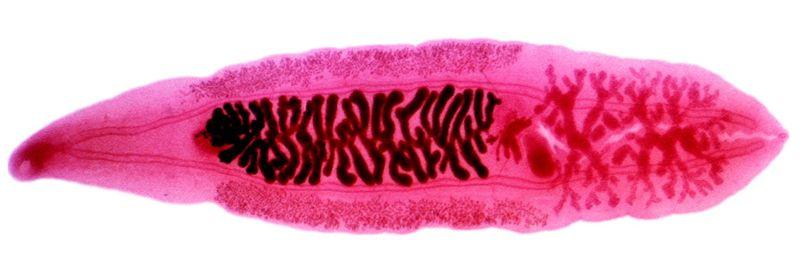

Clonorchis adult

Paragonimus adult

Shistosoma mansoni male